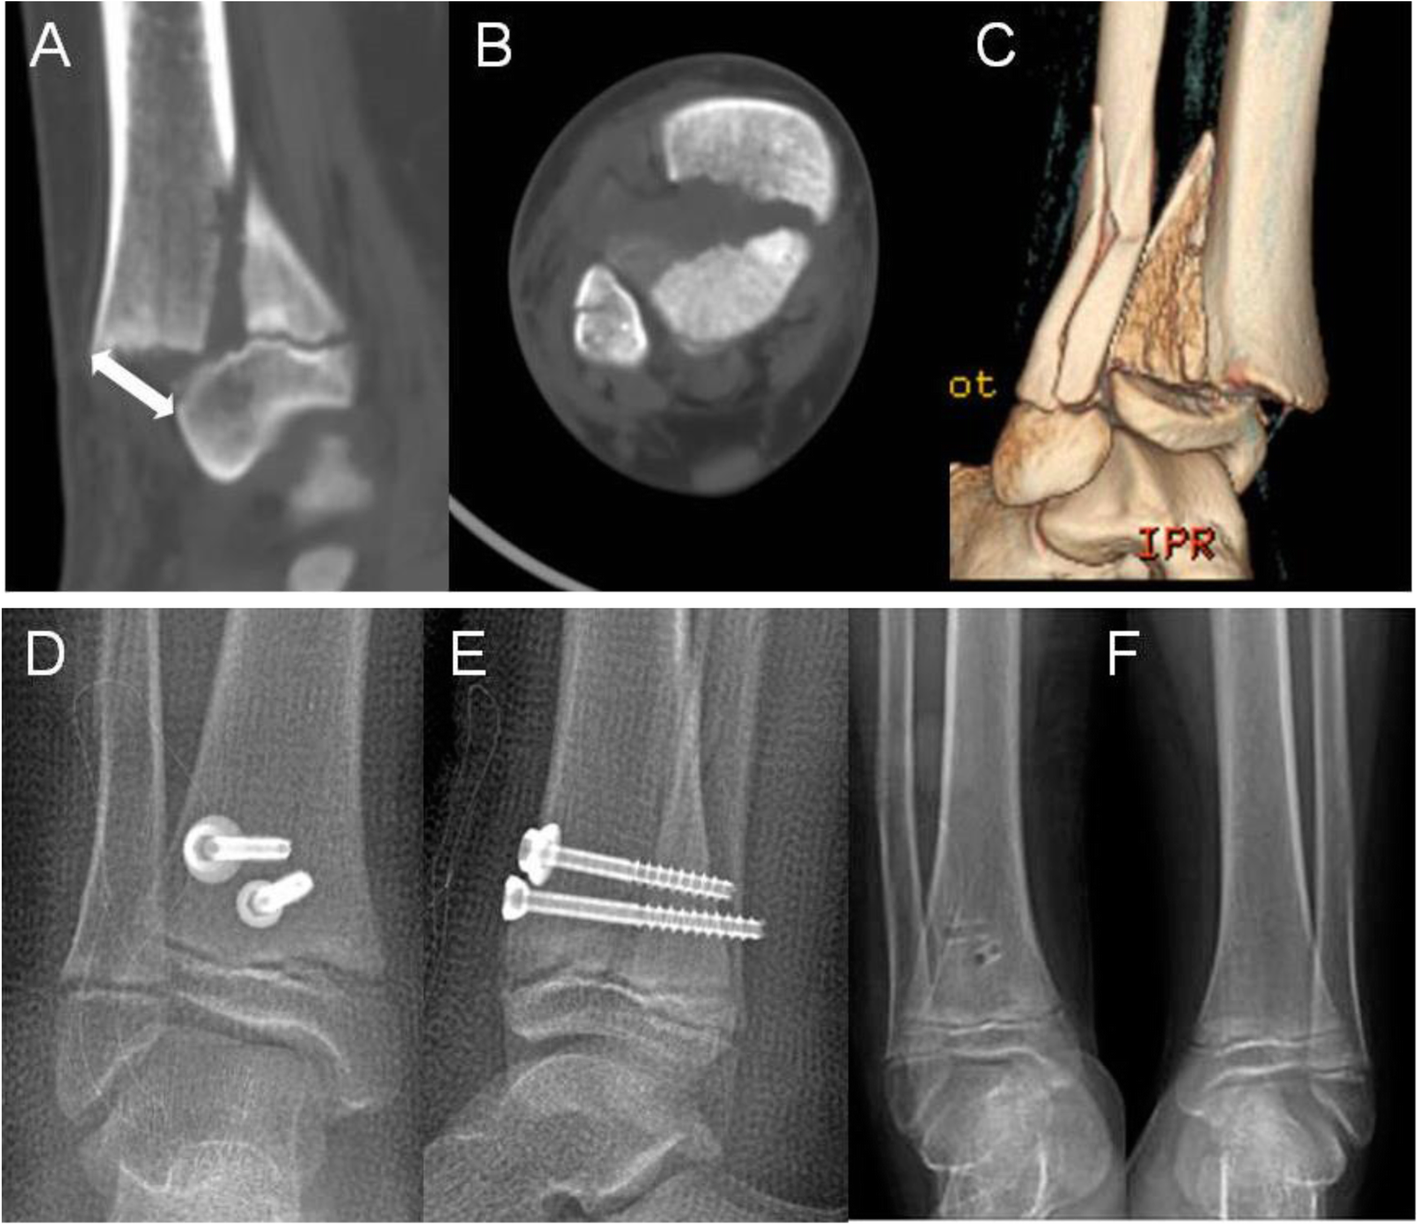

Fig. 2

A 12-year-old boy. a–c, Sagittal, axial and 3D view demonstrated 15 mm displacement of the fracture (white double arrow ). d, e AP and lateral radiographs demonstrated the anatomical reduction immediately post operatively. f AP radiograph of bilateral ankle joints taken at 9-month follow-up showed symmetrically open physis as compared with the opposite side